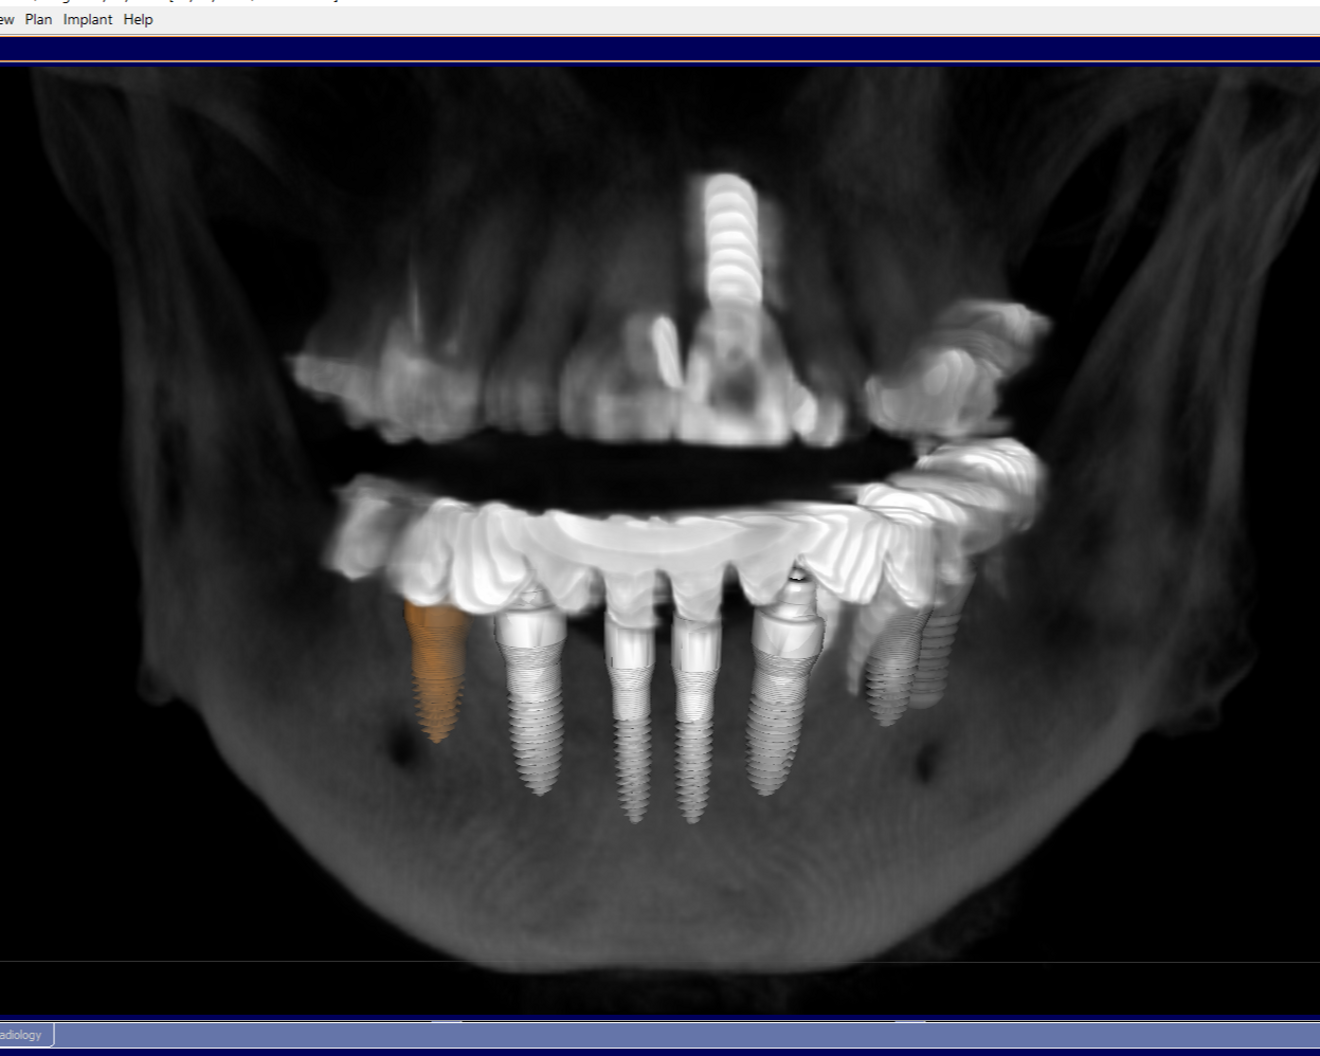

Fig. 4: Implant planning and parallelisation with YomiPlan.

Preoperative planning was performed using CBCT (Axeos and Galileos, Dentsply Sirona; Fig. 3) and YomiPlan planning software (Neocis) to select and parallel all the implants (Fig. 4). Preoperative maxillary, mandibular and bite scans were taken with CEREC Primescan (Dentsply Sirona) and sent to the laboratory for a temporary mock-up (Fig. 5). This allowed the laboratory technician to pre-plan a temporary restoration and discuss implant positions and final prosthetic solutions.